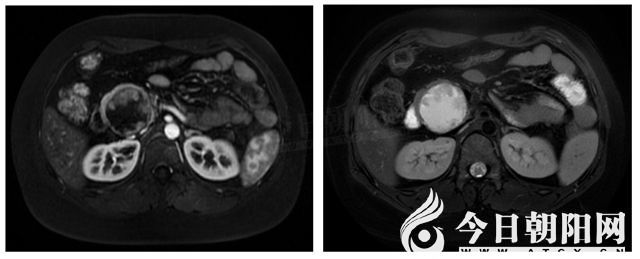

28歲的王女士因體檢發(fā)現(xiàn)胰頭腫物已經(jīng)有5年,這期間她咨詢(xún)過(guò)很多醫(yī)院,均被告知需要手術(shù)治療,甚至有可能行胰十二指腸切除術(shù),即普外科最復(fù)雜的手術(shù)之一。懷著忐忑的心情,王女士來(lái)到了市中心醫(yī)院肝膽胰脾外科就診。入院后,醫(yī)生對(duì)患者完善了常規(guī)的術(shù)前檢查,其腫瘤標(biāo)志物等各項(xiàng)實(shí)驗(yàn)室指標(biāo)均無(wú)異常,結(jié)合患者的增強(qiáng)MRI表現(xiàn),以寧純民教授、丁彥彬教授為核心的治療團(tuán)隊(duì)初步判斷患者的病灶為良性或低度惡性的囊性病變。

由于患者比較年輕,若行胰十二指腸切除術(shù),則術(shù)后可能會(huì)對(duì)患者造成血糖異常等諸多不良影響。經(jīng)過(guò)科室討論后,治療團(tuán)隊(duì)最終為她制定了個(gè)體化的治療方案——保留十二指腸的胰頭切除術(shù)。術(shù)中的情況和預(yù)期基本相符,術(shù)中病理證實(shí)患者的病灶是胰腺實(shí)性假乳頭狀腫瘤——一種低度惡性的腫瘤,沒(méi)有侵及周?chē)难埽瑢幖兠窈投┍蚵?lián)手為患者施行了保留十二指腸的胰頭切除術(shù)。手術(shù)過(guò)程順利,患者術(shù)后未出現(xiàn)嚴(yán)重的并發(fā)癥,并于術(shù)后第10日順利出院。